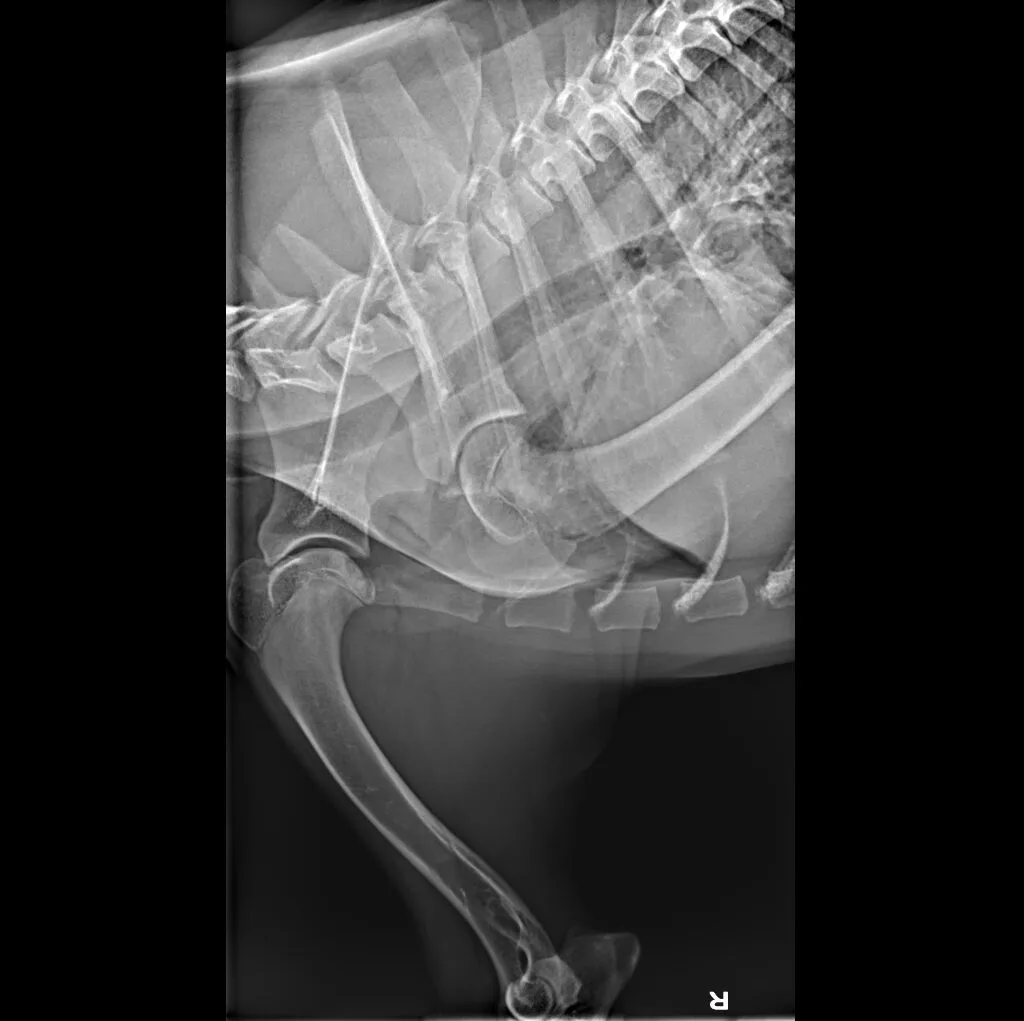

At Grand Ave. Pet Hospital, we utilize digital radiography to diagnose and monitor a wide range of medical conditions in pets. Digital X-rays provide clearer images, faster results, and safer radiation levels, ensuring the best possible care for your furry companion.

Digital radiography offers superior imaging quality and precision compared to traditional X-ray techniques. It allows us to detect hidden health issues early, leading to faster and more effective treatments.

🔹 Lameness & Joint Issues – Identifying fractures, arthritis, and mobility concerns